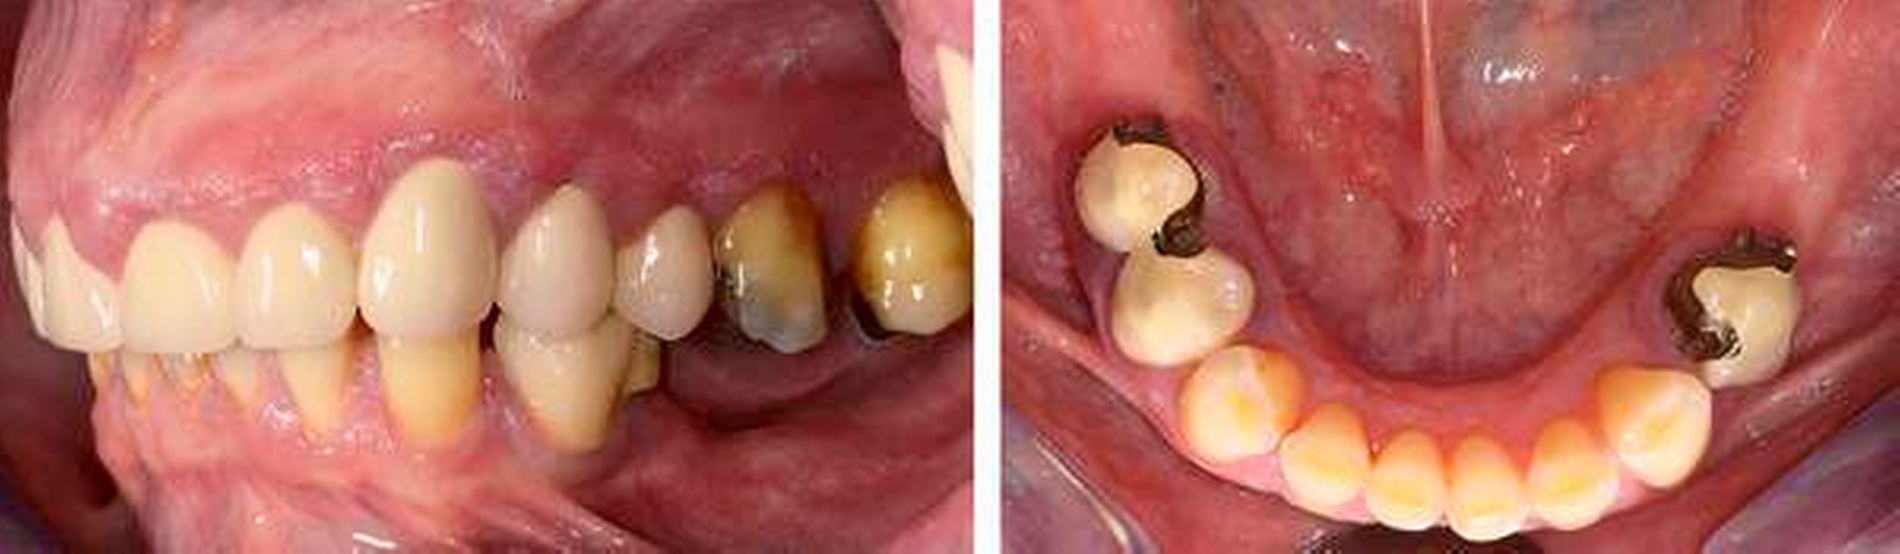

Anamnese: Die 53-jährige Frau stellte sich im Januar 2015 in der Poliklinik für Parodontologie des Universitätsklinikums Dresden vor. Sie war von ihrer Hauszahnärztin mit der Bitte um Diagnostik und Therapie der gingivalen Größenzunahmen (Abbildungen 1a bis 1e) überwiesen worden. Die Patientin gab an, dass die Vergrößerung der Gingiva vor ungefähr einem Jahr begonnen habe und diese sie mittlerweile in ihrer häuslichen Mundhygiene einschränke. Die Benutzung von Hilfsmitteln zur Interdentalraumpflege sei nicht mehr möglich und die Gingiva blute seitdem häufig. Den Kaukomfort ihres 2009 angefertigten Zahnersatzes empfand sie als gut. Als Grund für die multiplen endodontischen Therapien und die Überkronungen an den Zähnen 15, 13 bis 22 sowie 24 und 25 gab die Patientin starke Abrasionen an. Seit dem Auftreten der Gingivawucherungen ergänzte sie auf Anraten ihrer Hauszahnärztin die häusliche Mundhygiene einmal täglich mit Chlorhexidingel, 1-prozentig.

Befund: Bei der klinischen Untersuchung zeigten sich vestibulär und oral im Bereich der Papillen und der befestigten Gingiva generalisierte Gingivawucherungen im Oberkiefer (OK) und im Unterkiefer (UK). Die Interdentalräume waren aufgrund der Gingivawucherungen nicht für Hygienehilfsmittel durchgängig. Der Parodontale Screeningindex (PSI) wies im OK die Codes 3/3/4, im UK die Codes 3/1/3 auf. Der daraufhin erhobene Parodontalstatus (Abbildung 2) zeigte im OK Sondierungstiefen bis 7 mm mit Furkationsbeteiligungen Grad I (Zähne 16, 26, 27). Im UK betrugen die Sondierungstiefen bis zu 4 mm. Die Zahnbeweglichkeit an den Zähnen 16, 26 (Grad I) und 27 (Grad II) war erhöht.

Der Plaqueindex PCR betrug 72 Prozent [O`Leary TJ et al., 1972] und der gingivale Blutungsindex GBI 75 Prozent [Ainamo J et al., 1975]. Das alio loco angefertigte Orthopantomogramm (Abbildung 3) zeigte horizontalen Knochenabbau bis zu einem Drittel der Wurzellänge in beiden Kiefern. Die Zähne 16 und 26 wiesen einen Knochenabbau > 2/3 der Wurzellänge auf. Am Zahn 27 mesial erreichte der Knochenabbau die Wurzelspitze; zudem war der Zahn elongiert und wies eine Kippung nach distal auf. In einer ersten Einzelzahnprognose wurden alle Zähne mit Ausnahme von Zahn 27 als sicher eingestuft. Prothetisch war die Patientin im OK mit einer Brücke (13 bis 15), Kronenblöcken (21/11, 21/22, 24/25) und Amalgamfüllungen an den Zähnen 16 und 26 sowie im UK mit einer geschiebeverankerten Modellgussprothese versorgt.

Sechs Wochen nach Deep Scaling und Root Planing erfolgte eine zweite Reevaluation mit Befunderhebung [MacNeil RL et al., 1999]. Erhöhte Sondierungstiefen lagen nur noch an den Zähnen 27 (5 mm) und 34 (4 mm) vor (Abbildung 4). Die Gingivawucherungen hatten sich vollständig zurückgebildet (Abbildungen 5a bis 5e). Die Plaque- und Blutungsindizes waren niedrig und stabil (20 Prozent). Abschließend wurde eine PZR zusammen mit einer subgingivalen Reinigung an den Zähnen 27 und 34 durchgeführt. Die Prognose der Zähne mit Ausnahme des Zahns 27 ist weiter als sicher einzustufen. Zahn 27 bleibt kritisch. Dies ist durch den Attachmentverlust von 10 mm mesial und den Lockerungsgrad II begründet. Aufgrund der kompromittierenden parodontalen Situation und der eingeschränkten prothetischen Wertigkeit könnte bei Beschwerden an Zahn 27 neben einer chirurgischen Taschenelimination auch eine Extraktion erwogen werden. Die bisherige prothetische Versorgung könnte dann im Konzept einer verkürzten Zahnreihe belassen werden [Fueki K et al., 2015; Levey C et al. 2015]. Da die Patientin vorerst keine weitere Therapie an Zahn 27 wünschte, musste an dieser Stelle von einer chirurgischen Taschenelimination abgesehen und der Zahn belassen werden.